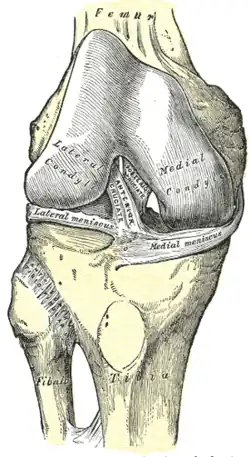

Kniekehlgelenk

Das Kniekehlgelenk (Articulatio femorotibialis) ist das eigentliche, für die Beugung des Knies zuständige Gelenk. Es ist eine Mischung aus einem Rad- und einem Scharniergelenk, die man als Drehscharnier-, Drehwinkel- (Trochoginglymus) oder bikondyläres Gelenk bezeichnet (ermöglicht somit die Beugung und Streckung, sowie im 90° gebeugten Knie eine leichte Ein- und Auswärtsdrehung) und befindet sich zwischen den nach außen gekrümmten Oberschenkelknorren und dem Schienbeinplateau. Es muss großen Belastungen standhalten, gleichzeitig aber ausreichende Beweglichkeit ermöglichen.

Menisken

Da die miteinander in Verbindung stehenden (artikulierenden) Gelenkflächen nicht genau aufeinander passen, wird diese „Ungleichheit“ (Inkongruenz) durch halbmondförmige Faserknorpelscheiben, die Menisken ausgeglichen, die den Drehbewegungen folgen können. Eine weitere Aufgabe der Menisken besteht in der Vergrößerung der Kontaktfläche zwischen Schienbein und Oberschenkelknochen.

Man unterscheidet einen Innenmeniskus (Meniscus medialis), der C-förmig, größer und etwas unbeweglicher (da mit dem Innenband verwachsen) ist, und einen Außenmeniskus (Meniscus lateralis), der kreisförmig, kleiner und beweglicher ist (da er mit keinem Seitenband verwachsen ist). Die Menisken sind im Querschnitt keilförmig. Die hohe Kante liegt außen, die niedrige innen. Da die Oberschenkelknochen genau in der Mitte direkt auf dem Schienbeinplateau und peripher auf den Menisken aufliegen, tragen diese einen wesentlichen Teil der Last.

Beim Bewegen des Kniegelenks werden die Menisken von den Oberschenkelkondylen (auch: 'Oberschenkelknorren', abgeleitet von „Baumstumpf“ oder „Holzklotz“, siehe auch: Oberschenkelknochen) vor sich her geschoben: Bei Beugung rollen und gleiten die beiden Kondylen zurück und drängen die Menisken nach hinten, bei Streckung gelangen sie wieder nach vorne. Bei Auswärtsdrehung des Unterschenkels wird der Außenmeniskus auf dem Schienbein nach vorne geschoben, der Innenmeniskus zurückgezogen, bei der Einwärtsdrehung ist es umgekehrt.

Die Menisken können vorne durch ein kurzes, kräftiges Band (Ligamentum transversum genus) verbunden sein, das aber variabel ist und keine Verbindung zum Schienbeinplateau hat. Als eigentliche Verankerung der Menisken strahlen die Fasern der Vorder- und Hinterhörner in das Schienbeinplateau ein und begründen damit die beträchtliche Zugfestigkeit. Zusätzlich können variabel angelegte Bänder (Ligamenta meniscofemoralia) den lateralen Meniskus mit dem inneren Oberschenkelknorren verbinden.[10]